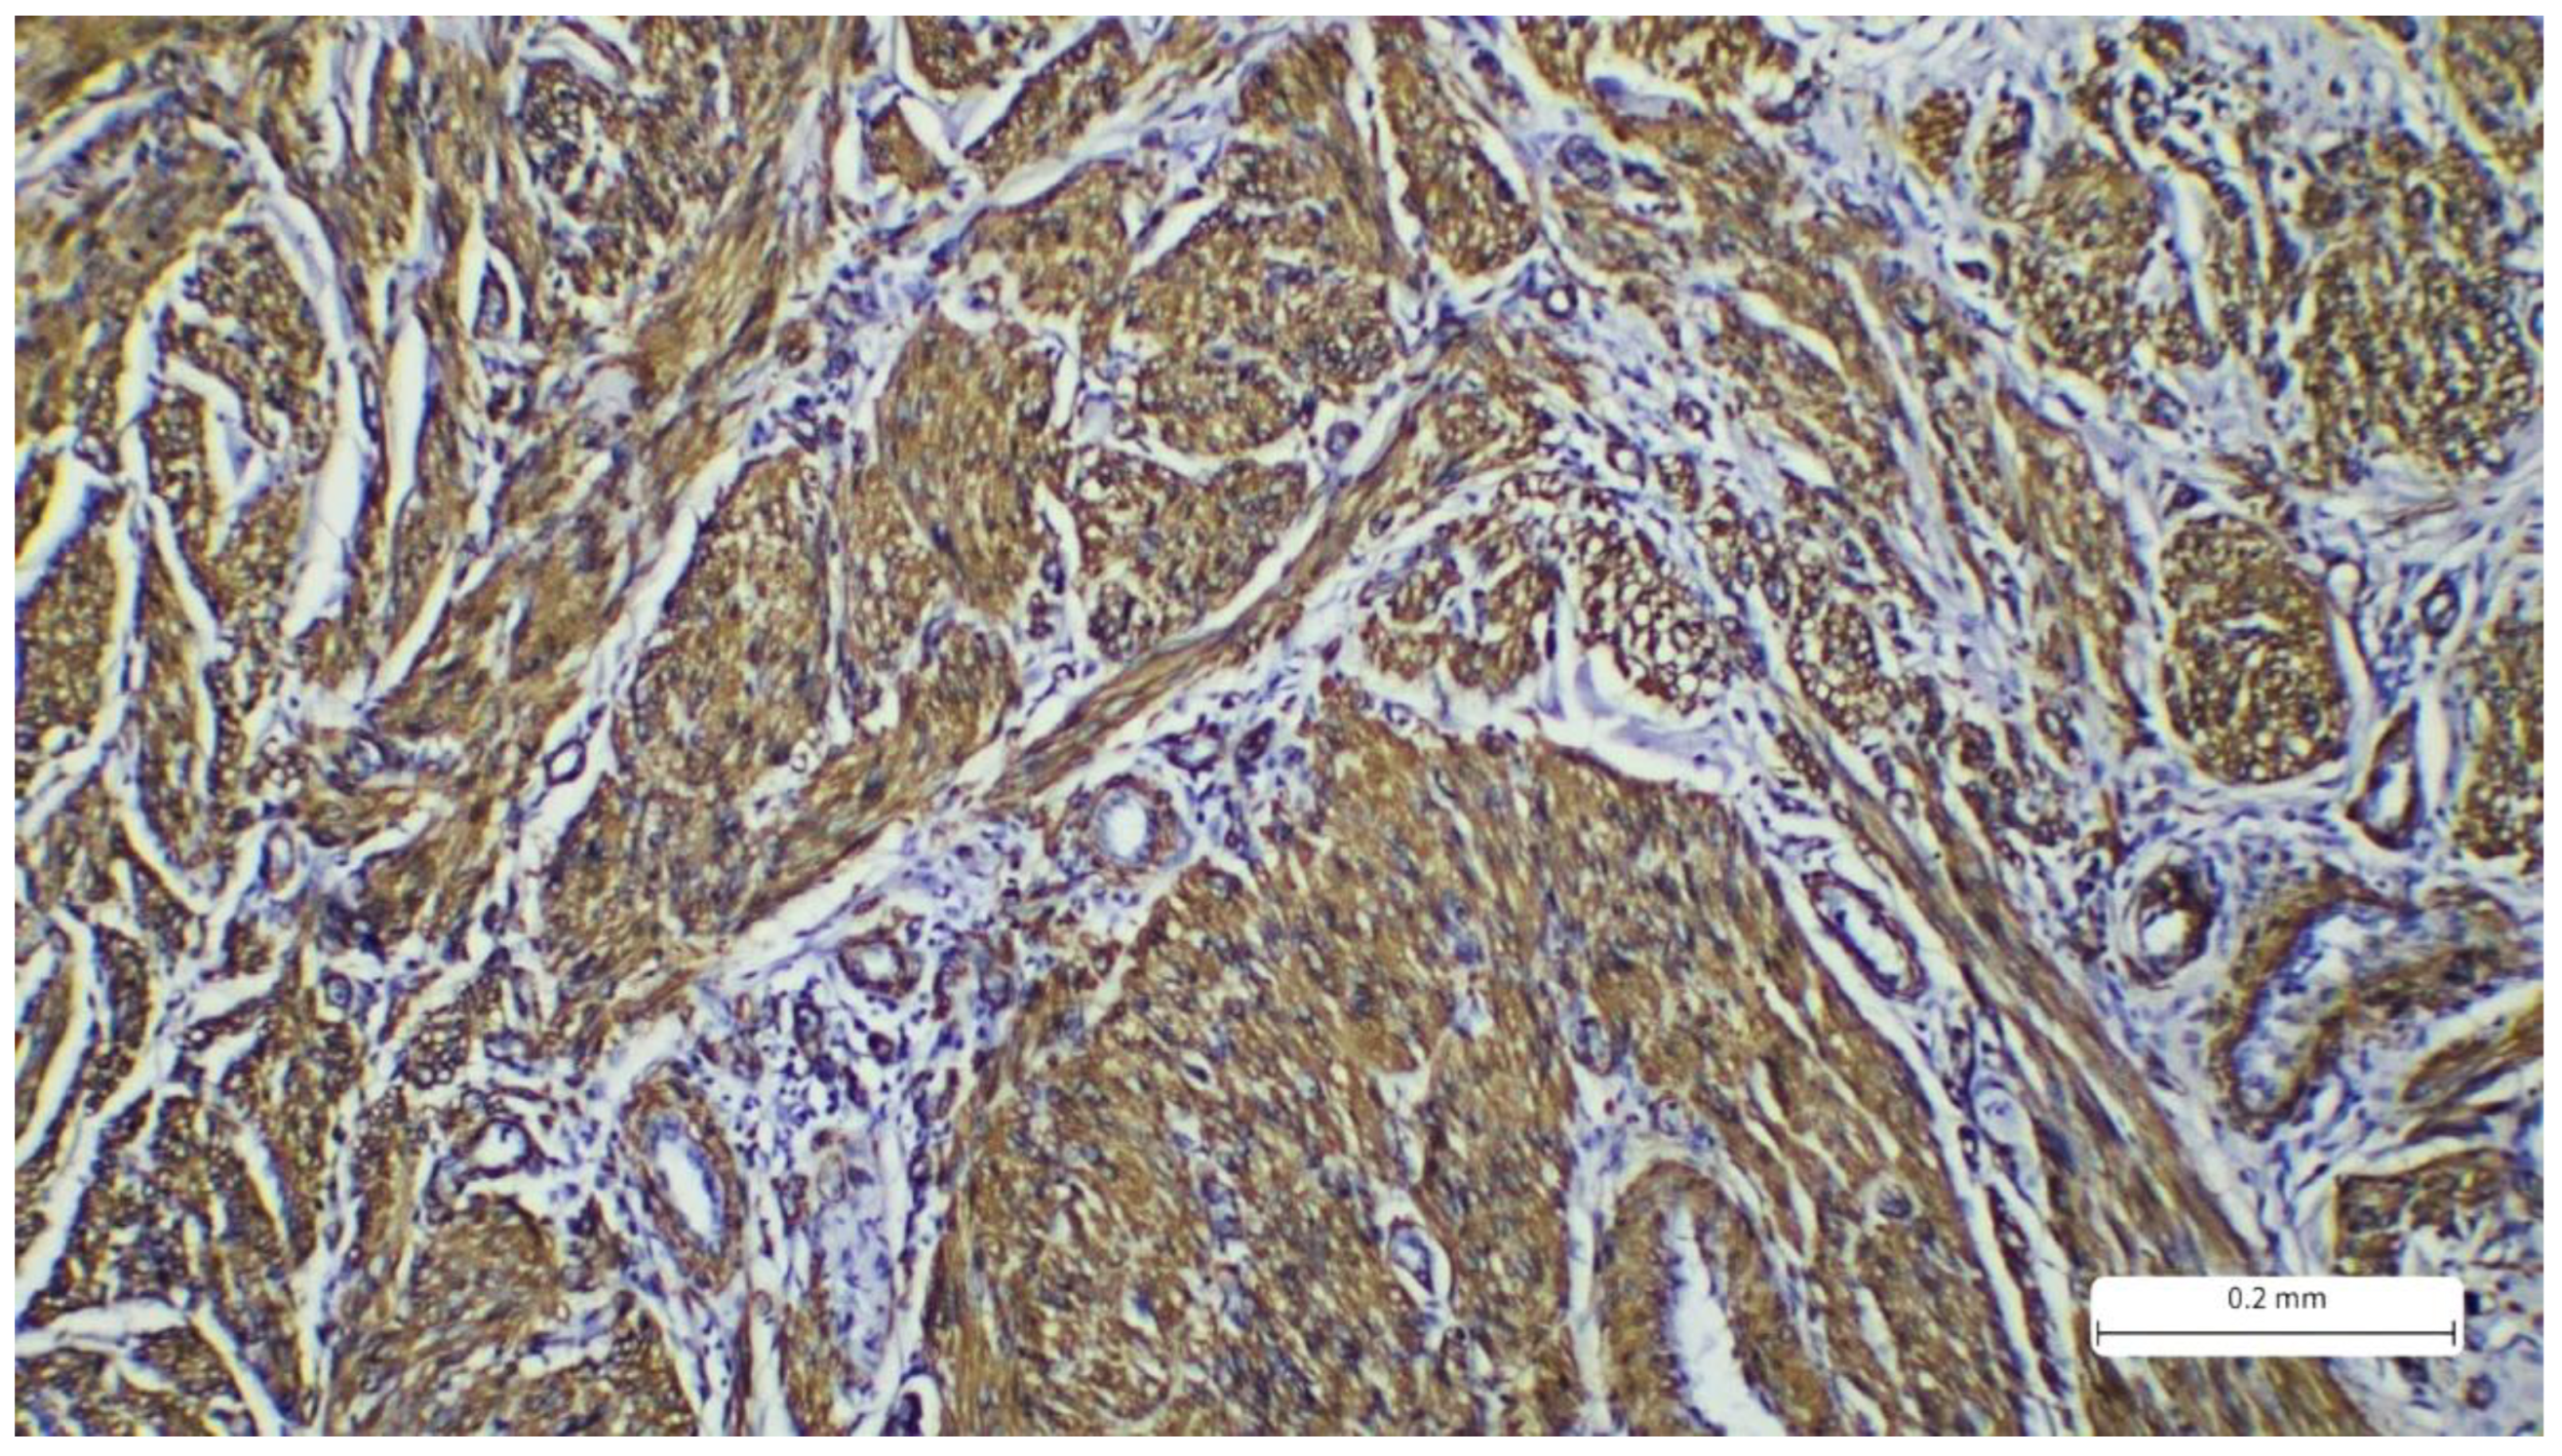

Figure 4. Immunohistochemistry reaction with cytoplasmic marker SMA showing positivity in the tumor spindle cells.

Figure 5. Immunohistochemistry reaction with cytoplasmic marker desmin showing positivity in the tumor spindle cells.

The immunohistochemistry profile showed strong positivity for SMA (Actin, smooth muscle (1A4), Mouse Monoclonal Antibody, CELL MARQUE) and desmin (CONFIRM anti-Desmin (DE-R-11) Primary Antibody, VENTANA). Markers S100 and CD68 were negative. The Ki67 proliferation index was expressed in 30% of tumor cells. The morphological and immunohistochemical findings confirmed the diagnosis of cutaneous leiomyosarcoma, grade I, according to the AJCC (American Joint Committee on Cancer) and FNCLCC (Fédération Nationale des Centres de Lutte Contre Le Cancer) grading systems. This grade is determined by the following parameters: differentiation, mitotic activity, and necrosis. For differentiation, the tumor receives a score from 1 to 3, where 1 represents sarcomas that resemble normal adult mesenchymal tissue, 2 represents sarcomas for which histologic type is certain, and 3 represents undifferentiated tumors. Mitotic activity scores from 1 to 3, where 1 is given for 0-9 mitoses/10 HPF, 2 for 10-19 mitoses/10 HPF, and 3 for more than 20 mitoses/10 HPF. Tumor necrosis scores range from 0 to 2, where 0 has no necrosis, 1 has less than 50% necrosis, and 2 presents with more than 50% necrosis. These scores are added to determine the grade. Our patient received 1 for differentiation, 2 for mitoses, and 0 for necrosis, totaling a score of 3, which places the case in the FNCLCC category G1 [8].

Microscopic examination of the tumor samples provides crucial data for the patient’s prognosis. On the HE stains, we can observe details regarding the tumor's architecture and cytology. Typically, LMS presents solid proliferation, with tumor cells arranged in fascicles with storiform patterns. The cells are spindle-shaped, with eosinophilic cytoplasm and elongated nuclei that have a cigar-shaped appearance. Pleomorphism and atypia are evident, and the mitotic count is commonly high [1,15]. Despite these characteristics, HE staining alone is insufficient for diagnosis, as LMS can exhibit variability in these features and resemble other sarcomas with similar patterns (for example, tumors of neural or melanocytic origin). Thus, confirmation of the diagnosis is required, and immunohistochemistry is performed. Markers such as SMA (smooth muscle actin), desmin, and caldesmon are used to determine the myogenic origin. The tumor should be positive for at least two of these markers. Our case showed positivity for SMA and desmin. Caldesmon was not performed due to limited availability in our laboratory. Additionally, the Ki-67 proliferation index was expressed in 30% of the tumor cells. Neural origin (malignant peripheral nerve sheath tumor) and melanocytic origin (spindle cell melanoma) were excluded based on IHC, not only due to positivity for myogenic markers but also due to negativity for S100. For spindle cell melanoma, markers like PRAME and SOX10 would exhibit higher specificity, but S100 is highly sensitive for melanocytic lineage. Atypical fibroxanthoma (AFX), a key differential diagnosis of LMS, was also excluded because the CD68 marker was negative. AFX also presents additional details such as the presence of epithelioid or multinucleated cells, which were absent in our case. Other spindle cell tumors, such as dermatofibrosarcoma protuberans (DFSP), also enter the differential diagnosis. However, this neoplasm typically exhibits a storiform pattern with invasion of the hypodermis, a classic aspect known as “honeycomb”, a feature which is absent in the usual stain in our case. In addition, the mitotic index is low, and the tumor exhibits CD34 positivity. The CD34 marker is essential for DFSP diagnosis and differential diagnoses with storiform tumors, and its positivity excludes LMS [16,17,18,19,20,21].